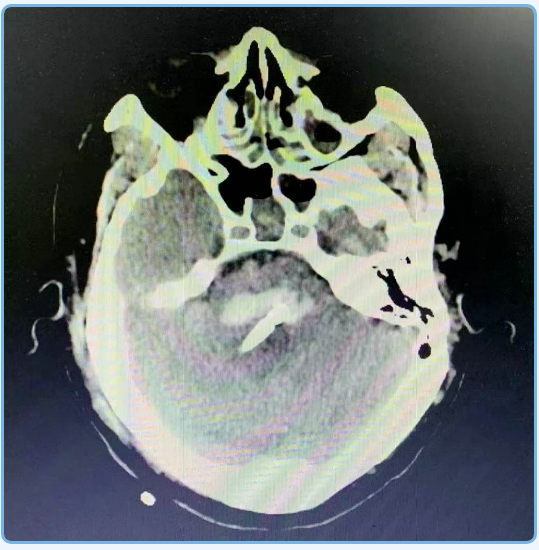

神经外科杨孔宾主任手术团队在全面评估后,诊断何叔为脑干出血。杨主任手术团队立刻通过机器人定向穿刺脑干血肿引流术,成功为何叔引流血肿。然而何叔脑部血肿虽已引流干净,生命体征也平稳, 脱离了呼吸机,但仍一直处于昏迷状态,经过3个月的各种其它康复促醒手段,仍未苏醒,被判定为植物状态。